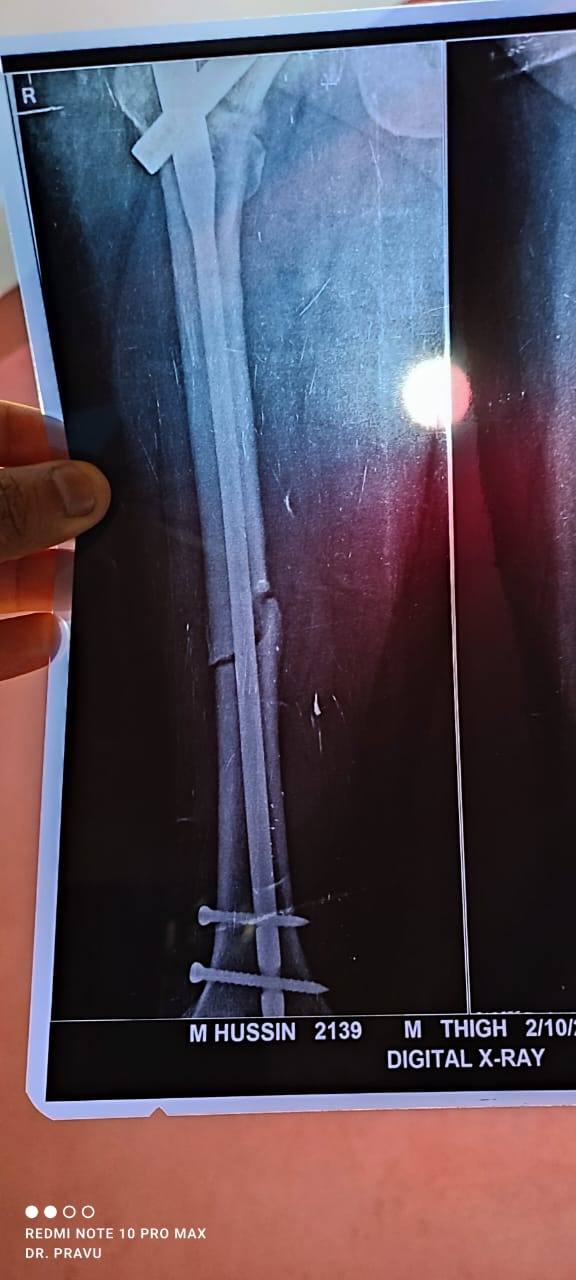

Ezaz Hussain